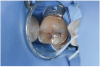

To diagnose pit-and-fissure caries, clinically the tooth being assessed should first be wet, and the practitioner evaluates its pits and grooves for any decalcification, which typically presents as a chalky white area that follows the depth of the groove (Figure 10 and Figure 11). This finding with the tooth being wet defines an ICDAS code 2 lesion. Next, the grooves are dried completely using a 5-second air stream, and the clinician notes any areas of chalkiness in the now-dry grooves. Any such area of chalky decalcification noted only after drying would represent an ICDAS code 1 lesion (Figure 8 and Figure 9). Code 1 and/or code 2 lesions are classified as CCS code 1 initial lesion. If no chalkiness is noted in either a wet or dry groove or pit, the tooth structure is classified as sound and documented as ICDAS and CCS code 0 sound structure (Figure 6 and Figure 7). The presence of stain and hypocalcification should be disregarded.

Fig 6. ICDAS code 0: Clinical appearance of stained fissure with no evidence of shadow or decalcification after drying.

Figure 6

Fig 7. ICDAS code 0: Sectioned tooth confirms stain not indicative of carious penetration of fissure.

Figure 7